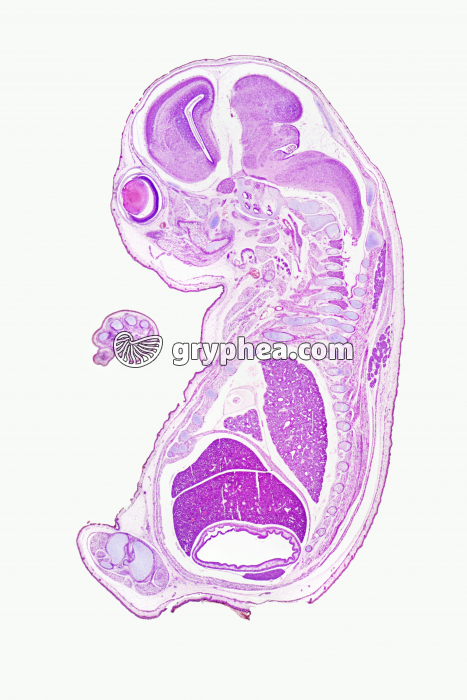

Embryon de souris CL coupe totale x1,5

Auteur : Hervé Conge

Thèmes associés : Embryologie

embryologieembryoncellules embryonnairespoilpeaucellules pigmentairestégumentstade embryonnairedéveloppement embryonnairemétamèrechordesystème nerveuxorganes embryonnairesorganestissuembryonnairecellules de l’embryonorganismeoeufannexe embryonnairefécondation